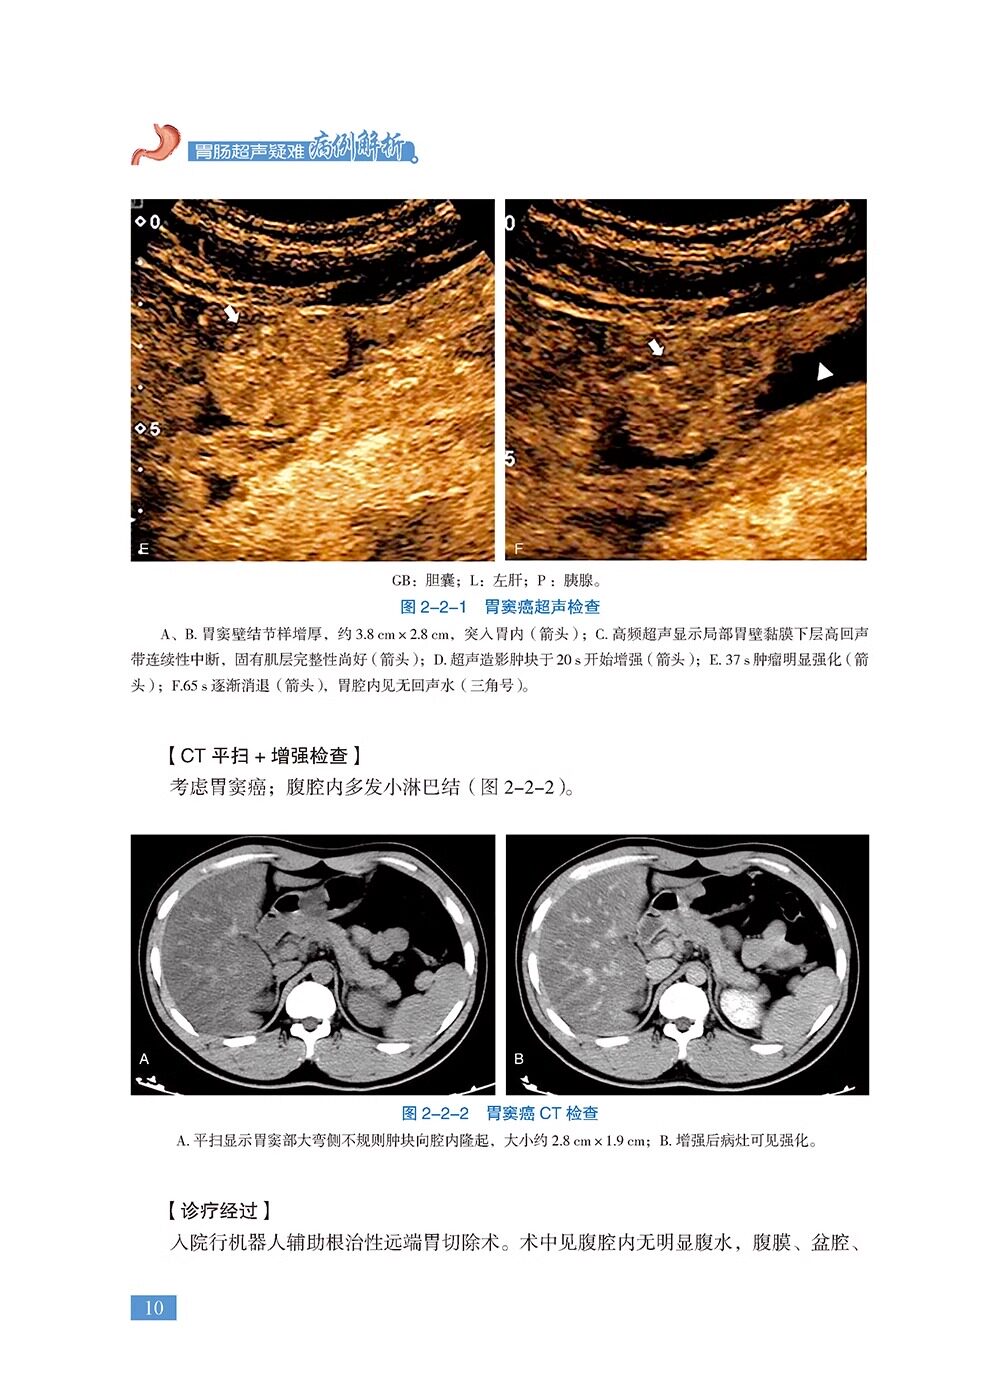

本书是《胃肠疾病超声诊断学》的姊妹篇,共18章,精心挑选了120个胃肠超声经典病例、疑难病例、罕见病例及误诊病例。涵盖各种胃肠道肿瘤、消化性溃疡、炎症性肠病、急腹症、先天异常、胃肠周围血管疾病等内容。每个病例从病史、体格检查、实验室检查、超声检查、其他影像检查、诊疗经过、病理诊断等方面进行详细阐述,并针对病例的超声特征及误诊原因等进行精准解析。全书精选了700余幅超声、CT、MRI、病理等图片,内容丰富、图文并茂,具有很强的实用性和指导性。适合各级超声医师及相关学科临床医师、医学院校师生阅读。